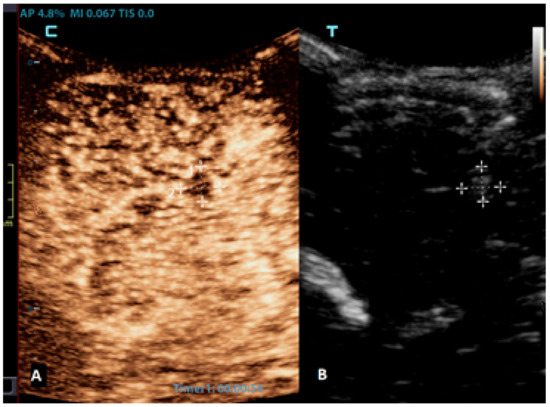

Brain tumors are the most common solid tumors in the pediatric population and are the second most frequent type of childhood cancer overall. While these tumors can occur at any age, they are most prevalent in children aged 3–7 years. Tumors in neonates and infants up to the age of 2 years typically occur in the supratentorial region, while in children older than 2 years, they are more frequently found in the infratentorial region. There are more than a hundred different histological subtypes of brain tumors that have been recognized; the most common ones are pilocytic astrocytomas, brainstem gliomas, and medulloblastomas [58]. Imaging plays a vital role in the management of patients with brain tumors. The gold standard for brain tumor assessments is MRI. Advancements in neuroimaging MRI techniques, such as the use of diffusion-weighted imaging (DWI), spectroscopy, perfusion imaging, and functional MRI, provide additional information about the metabolism and physiology of these tumors, which can aid in their diagnosis and monitoring [59]. The value of CEUS in the management of brain tumors is expanding, but the information that is available so far is still limited. CEUSs can help in the detection of solid brain tumors because they are typically more vascularized than brain parenchymas are (Figure 4). However, its ability to differentiate between different subtypes is limited [60,61]. So far, it has been most extensively used in intraoperative settings for surgical guidance [62,63]. Neoplastic tissue shows a higher contrast enhancement compared to that of the normal surrounding brain parenchyma because of its higher vessel density. Thus, CEUSs allow the most precise guidance of the surgical procedure and is especially useful for resection control [60,64,65,66].

Figure 4.

A 6-month-old premature boy with an accidentally detected small lesion in the 4th ventricle. (A) The transverse reference grayscale ultrasound image through the left mastoid fontanelle. (B) The transverse CEUS image of the 4th ventricle demonstrates avid arterial and venous enhancement of the lesion (arrows). Findings were suggestive of choroid plexus papilloma; subsequent brain MRI scans confirmed benign aetiology of the lesion.

When an infection spreads to the brain parenchyma, it leads to cerebritis, which can progress to abscess formation. Cerebritis can be focal, diffuse, or bilateral, and imaging can demonstrate the involvement of the grey matter, particularly using diffusion-weighted MR imaging and FLAIR sequences [75,78]. CEUSs, with their quantitative analysis of brain perfusions, have the potential to be used to diagnose this entity. Even more so, CEUSs can be used to diagnose brain abscesses and differentiate them from other focal brain lesions. Brain abscesses typically appear as a non-enhancing focal lesion with a hyper-enhancing rim (Figure 6) [79].

Figure 6.

A 2-month-old boy with acute lymphoblastic leukaemia and candida sepsis. Slowly growing hyperechoic lesions were detected using a brain ultrasound. (A) The sagittal CEUS image of the brain at 54 s after the application of contrast agent shows high signal intensity only at the rim of the lesion (crosses). Candida micro-abscesses were suspected and later confirmed using a brain MRI scan. (B) A sagittal reference grayscale ultrasound image shows a small hyperechoic lesion (plusses).